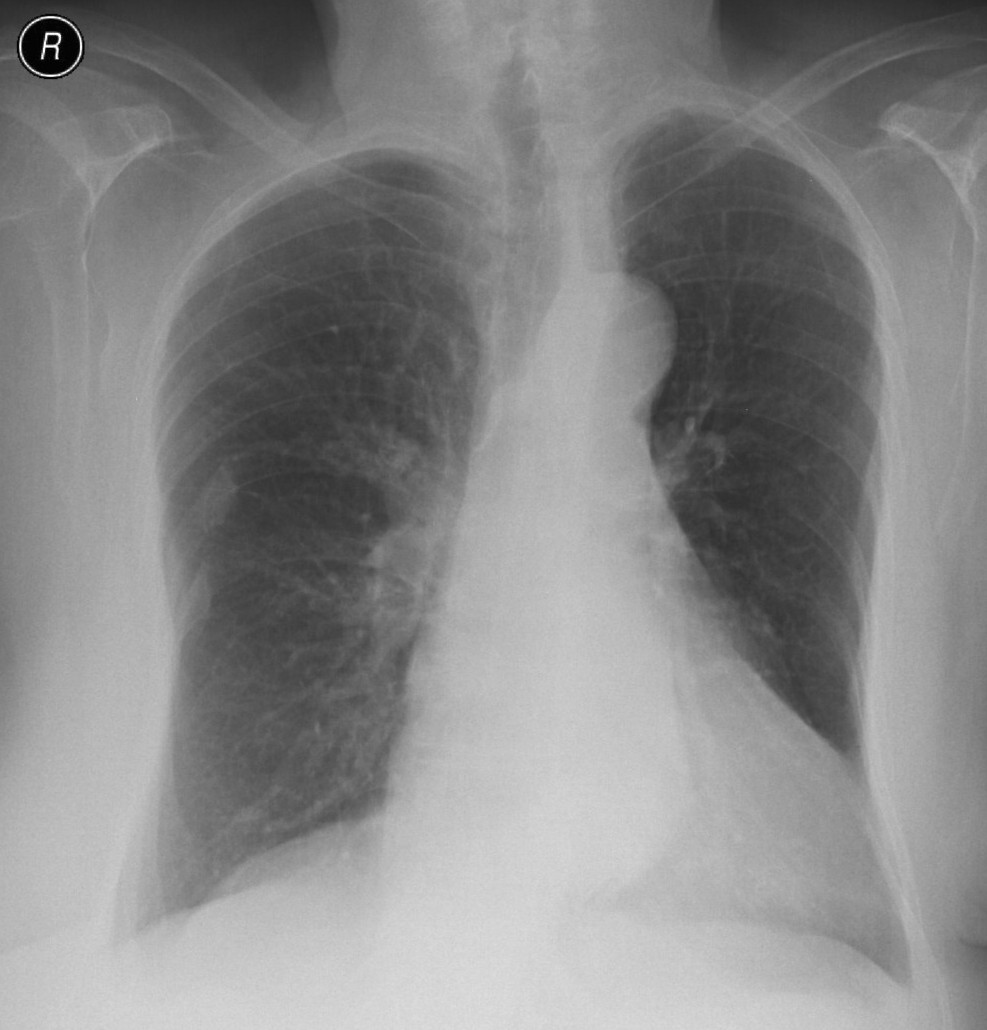

15. Atypical interstitial lobar pneumonia a.) CT b.) radiograph

45 year old man. He had a chill, serious cough, yellow-green tracheal excretion.

Left-sided lymphadenopathy next to the aortic arch on the left. Irregular infiltrations (opacities) in the lung parenchyma in subpleural and LUL dominance. (by the contribution of Zsuzsanna Monostori, MD, PhD)